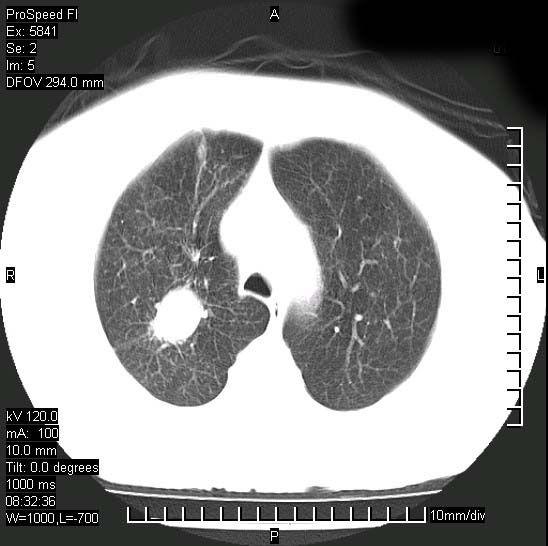

胸痛,咳嗽,气短一周,无发热。右上肺见一结节灶,边缘刺角,内见多个小钙化结节。考虑结核球?肿瘤? 余无异常没有上传。

考虑右肺上叶继发性肺结核,结核球形成。

慢性炎性病变,结核可能性大些。

胸膜是受侵的,考虑感染,结核球可能性大

考虑结核球,并胸膜局限性增厚!!

为什么不考虑肺癌????????????